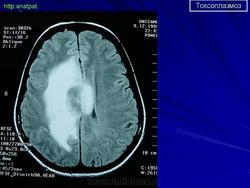

Токсоплазмоз

Церебральный токсоплазмоз.

Церебральный токсоплазмоз